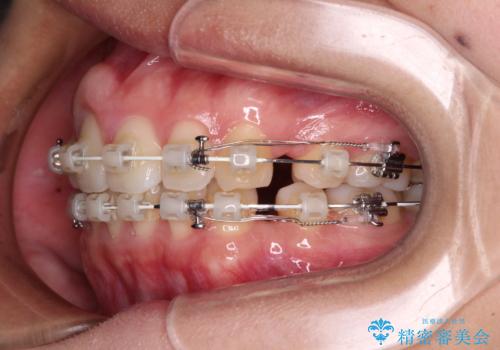

- 矯正装置

- 審美装置

- 1年8ヶ月

- 10-30回

- 前歯の出っ歯と口元の閉じにくさを気にして来院された患者様です。

口元を積極的に引っ込めるために、上下左右の小臼歯4本を抜歯することとしました。